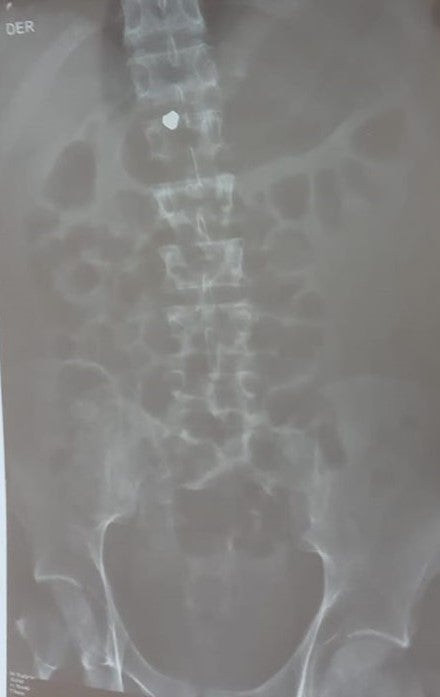

X-ray showing a pellet, believed to be lead, lodged in Jon Cordero’s spinal cord. Photograph courtesy of Jon Cordero’s family.